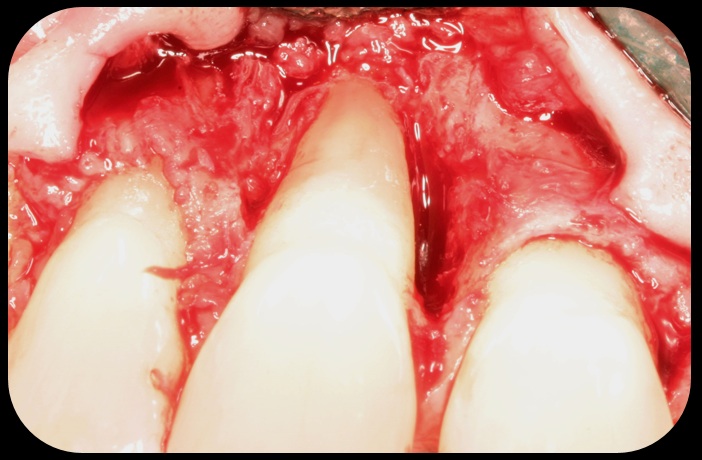

Facial bone loss and a mesial vertical defect.

Fig. 3

Application of enamel matrix derivative.

Fig. 4

Demineralized freeze-dried bone allograft.

Fig. 5

Evidence of clinical attachment gain.

Fig. 6

Then, too, are opportunities to prepare the site for regeneration by coupling therapies, applying an enamel matrix derivative, along with traditional bone grafts of demineralized freeze-dried bone allograft; potentially, gains in attachment with minimal probing depth and retained papilla may avoid the need for an implant (Figure 2 through Figure 7).